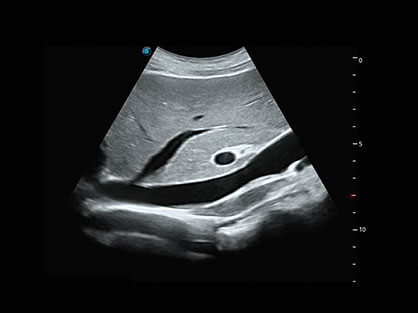

• 产科自动测量

自动获取标准切面,自动完成测量,帮助医生快速完成检查,同时提升测量准确性。